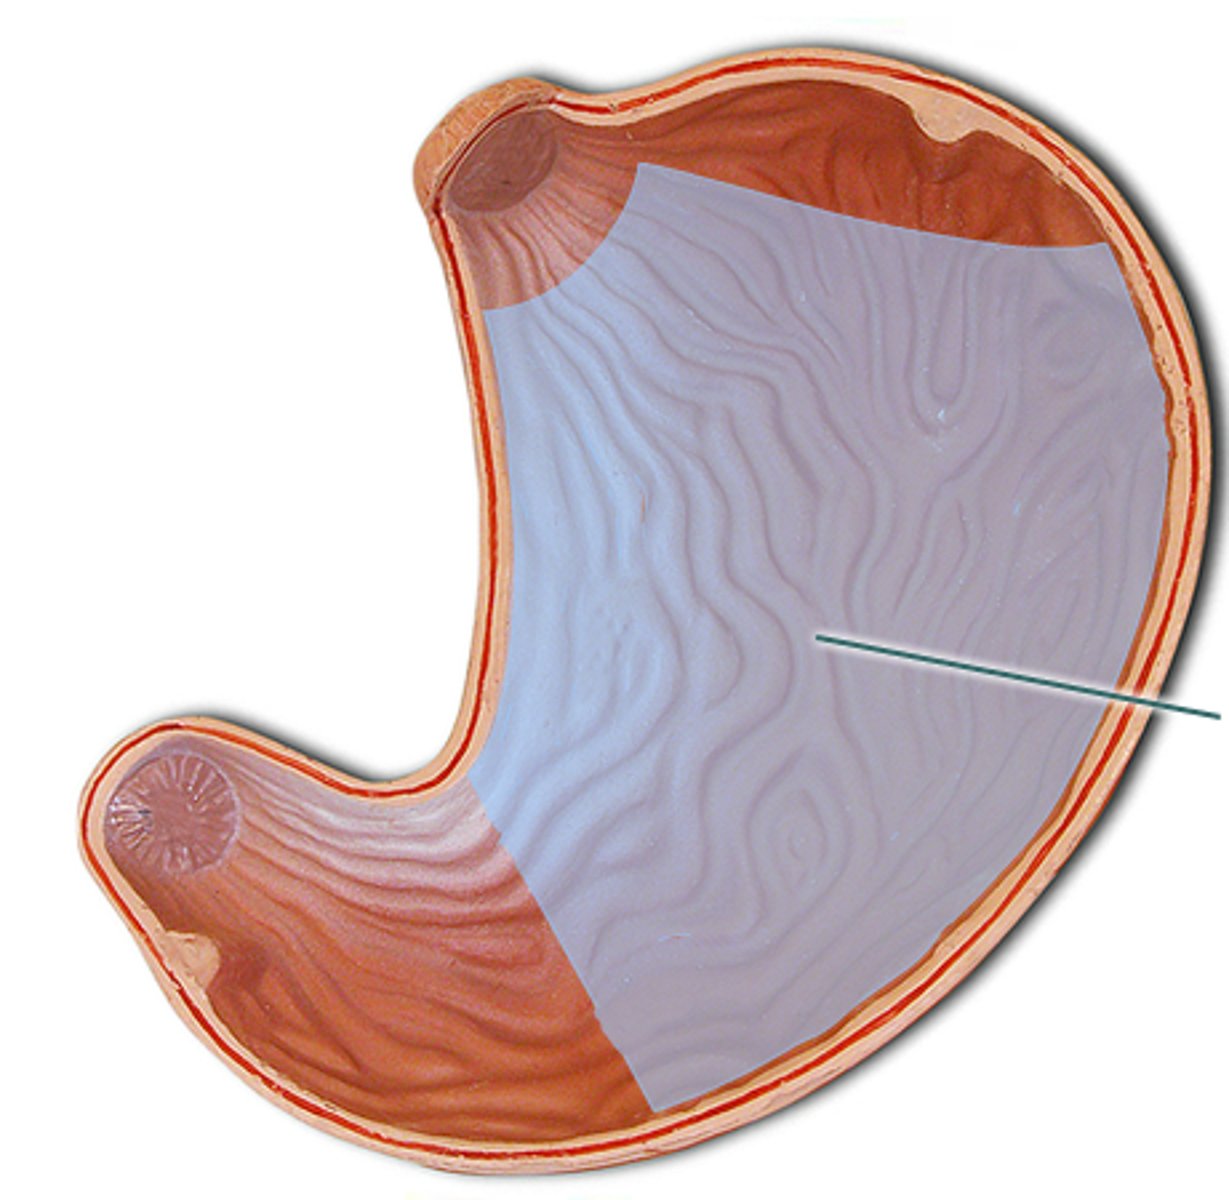

stomach

fundus

cardia

body

lesser curvature

greater curvature

cardiac sphincter / lower esophageal sphincter

pylorus

pyloric sphincter

rugae